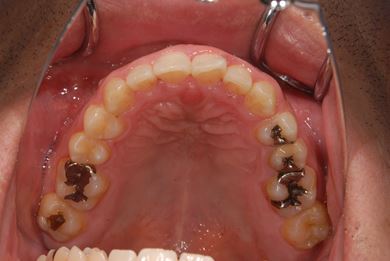

インプラントの症例写真 IMPLANT

抜歯即日スピードインプラント治療

| 性別/年齢 | 男性 / 38歳 | ||||||||||||||||||||||||||||||||

| 主訴 | 10年位前に虫歯治療をした右下奥歯のつめ物が取れ、再治療を受けた際にインプラントをすすめられたため、治療相談で来院。 | ||||||||||||||||||||||||||||||||

| 治療方針 | 抜歯と同時にインプラントを埋入し、治療期間を短縮する。 | ||||||||||||||||||||||||||||||||

| 治療内容 | インプラント1本(抜歯即日スピードインプラント)、ハイブリッドセラミッククラウン1本 | ||||||||||||||||||||||||||||||||